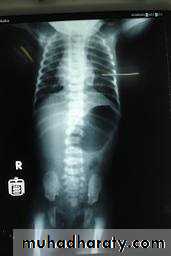

Infantile hydronephrosis ( PUJ OBSTRUCTION ):

IVU shows :

Marked dilatation of pelvis and may be extra-renal.

Calyceal dilatation is late and in advanced cases form foot shape PCS

The ureter is not seen and when it is seen looksnormal .

Delayed film with I.V. diuretic produce gross dilatation .